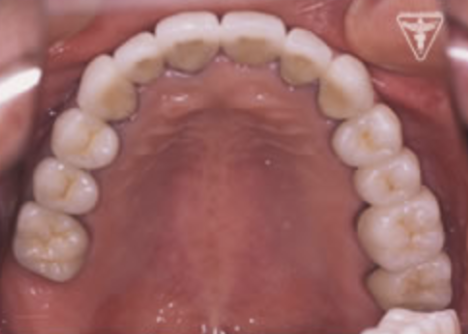

治療前

初診時の正面観・側方観・かみ合わせの面の状態を示します。

全顎に補綴処置が施され咬み合せの面がつぶれた様な状態となっている。